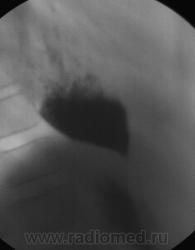

Неужели ахалазия?

Практически патогномоничная картина выраженной ахалазии кардии...

Именно так. Просто случай очень уж запущенный, редко такое увидишь - как в учебнике!

Посмотрите как выглядит грудная клетка при ахалазии 4-й степени